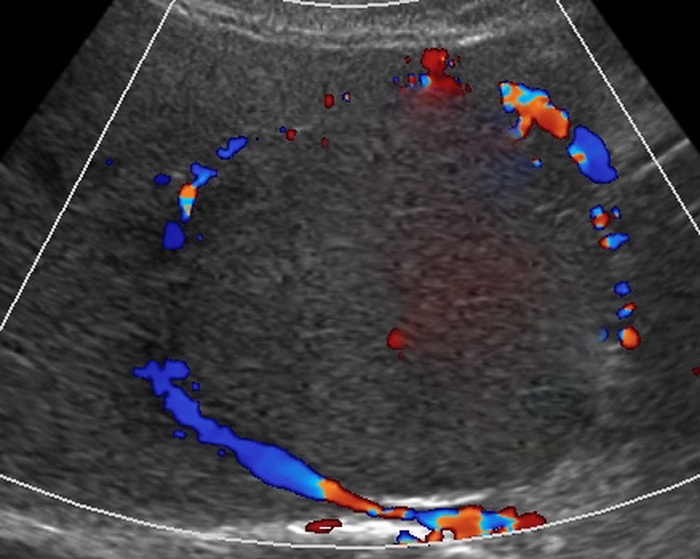

Hepatofugal flow